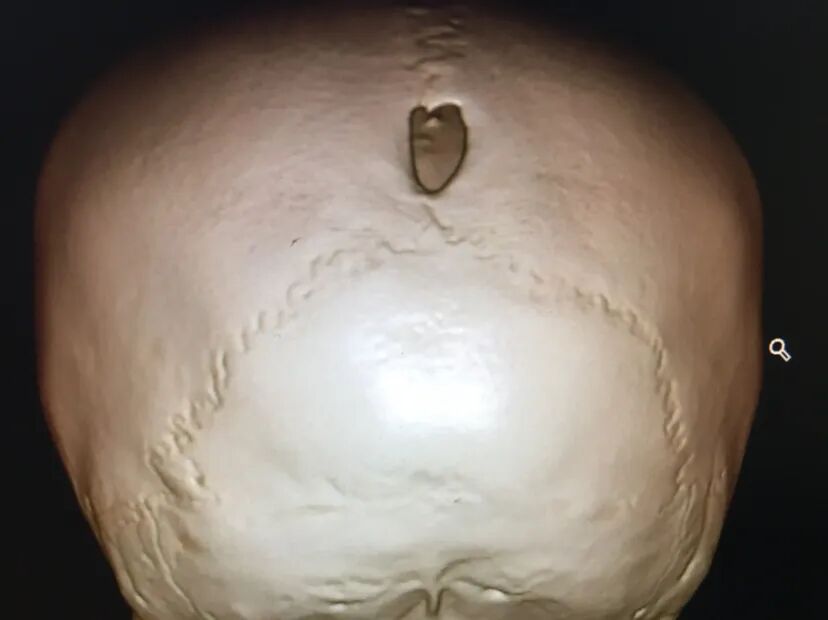

术前情况

儿童脑膜脑膨出是一种罕见的先天性疾病,病因不明,可能与胚胎时期神经管发育不良,中胚叶发育停滞,使颅骨发育缺陷出现颅裂,脑膜或脑膜脑组织经颅骨缺损处疝出颅外有关。临床表现为囊性肿物与头部相连,可在出生时发现,也可在出生几个月或几年后发现,哭闹或咳嗽时肿物增大,局部可扪及骨缺损的边缘。修补手术注意严密修补硬脑膜防脑脊液漏皮下积液。